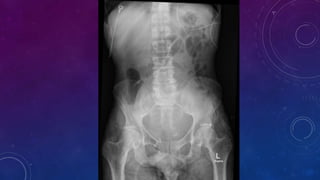

Bladder exstrophy or ectopia vesicae is characterized by deficient lower anterior abdominal wall

along with anterior walls of urinary bladder. The severity of these defects is widely variable. There

may be rudimentary posterior wall of urinary bladder.

The estimated incidence of bladder exstrophy is 1:10,000-50,000 live births. There is a recognized

male predilection with a male to female ratio of 3:1 . Most cases are sporadic.

Associated bony findings include widely separated pubic bones with absent symphysis pubis

leading to characteristic " waddling gait". This appearance on AP plain radiograph of the pelvis has

been likened to a manta ray swimming towards you (manta ray sign).

Bladder exstrophy is caused by a developmental defect of the cloacal membrane.

Associated defects in males include cryptorchidism, inguinal hernia and epispadia.

Associated defects in females include vaginal duplication and clitoral cleft. This is associated

prenatally with elevated maternal alpha feto protein levels.

Common complications include urinary incontinence, infertility, urinary infections and

increased risk of bladder malignancy in the extruded bladder. Treatment is with surgical

intervention (primary closure/excision with urinary diversion) and prognosis is generally

good.